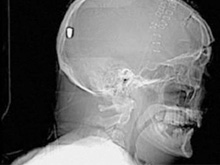

В Британии врачи нашли у пациента пулю в голове13.05.10 13:07 Прочтений новости 822 Общество В Британии у пациента, который поступил в клинику с подозрением на инсульт, врачи обнаружили пулю в голове. Но остается неизвестным, как мужчина получил ранение.Рентгеновские снимки головы показали, что в полости черепа находится инородный предмет. Мужчине сделали томографию головы, и врачи установили, что этим предметом является пуля. Как сообщается, 19 апреля 61-летний Питер Хесфорд упал во время работы у себя в саду. Позже его обнаружила жена, которая вызвала скорую. Мужчина оставался в сознании, но не мог говорить. Медики, прибывшие на место, заподозрили у Питера Хесфорда инсульт и доставили его в Больницу Уитеншо. Эксперты по баллистике, изучив снимки пациента, пришли к выводу, что пуля, застрявшая в затылочной области, могла попасть туда через глаз. Но мужчина не помнит, что именно с ним произошло. Врачи попытались удалить пулю, однако это оказалось невозможным из-за ее положения по отношению к окружающим структурам. Пациент остается в больнице, а его состояние расценивается как стабильное. Комментарии (всего 0)